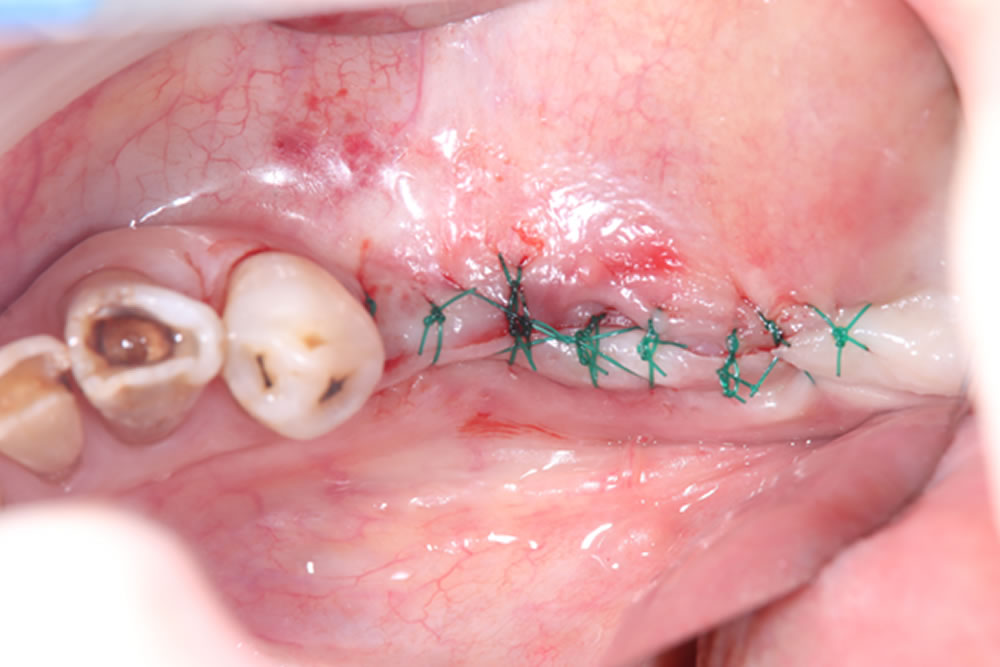

インプラント埋入手術

インプラント結合後に全顎精密仮歯の装着

インプラント手術から3ヵ月後、上下顎プロビジョナルレストレーション(仮歯)を装着しました。

- 上顎は総義歯

- 下顎左5・6番はインプラント

- 下顎その他はクラウン